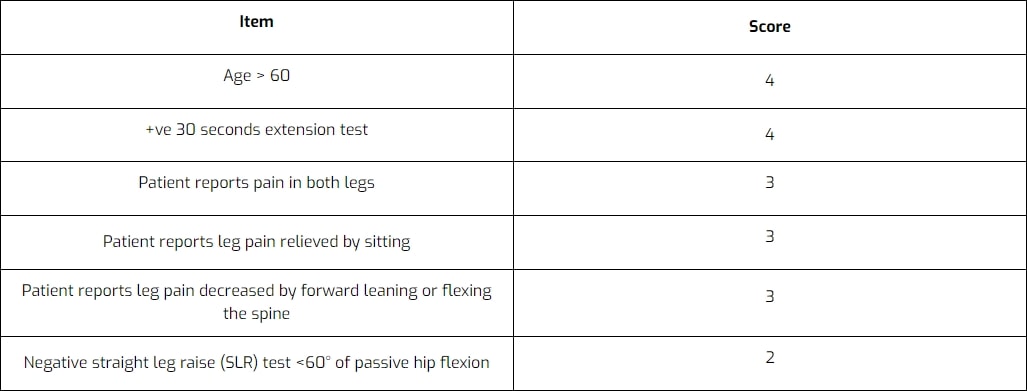

Dessa resultat är mycket lika den kliniska prediktionsregel som Cook et al. (2011) för att diagnostisera LSS:

Genevay et al. (2018) definierade kriterier som oberoende kunde förutsäga neurogen claudicatio på grund av LSS och som kan bidra till att skilja denna diagnos från radikulär smärta orsakad av diskbråck och aspekifik ländryggssmärta. En klassificeringspoäng med hjälp av en viktad uppsättning av dessa kriterier utvecklades. Den föreslagna N-CLASS-poängen sträckte sig från 0 till 19 med en cutoff (>10/19) för att uppnå en specificitet på >90,0% och en sensitivitet på 82,0%. De objekt som författarna fann var: